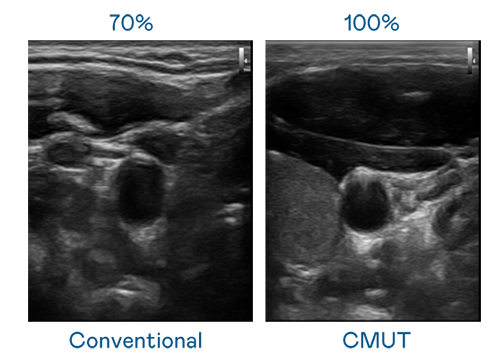

CMUT 技术是一种用电容式微机电元件来产生超音波讯号的技术。与传统 PZT 压电式技术相比,CMUT 频宽增加 30%,更宽频的超音波讯号让影像解析度大幅提升,是实现高影像品质医疗超音波扫描、促进精准医疗发展的关键技术。

大频宽带来超清晰影像

超音波影像的解析度高低,首先取决于探头能发出的讯号频宽。U8国际 CMUT 可提供高清晰的超音波讯号,提供高频宽、高灵敏度、影像纹理细节更高的超音波影像,协助医护人员缩短影像判读时间及利用精准的医疗影像进行诊断。